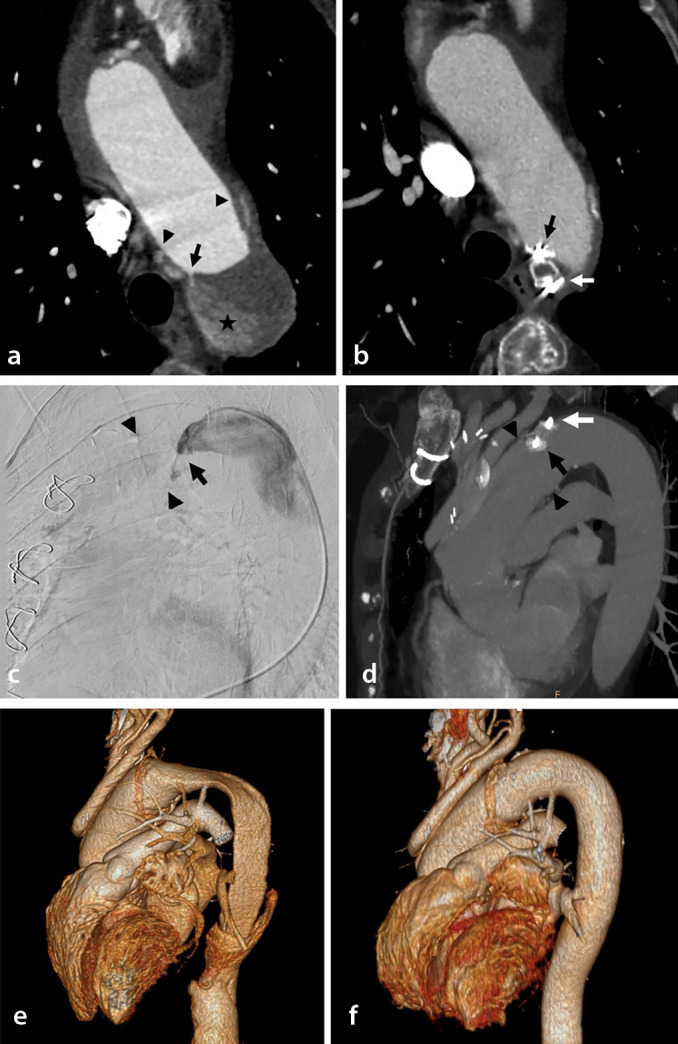

Methods: This retrospective monocentric study included patients treated by CFLO between 2003 and 2022 in the context of chronic AD with progressive descending aneurysmal evolution and persistent circulating false lumen (FL). The procedure was achieved with coils, plugs, and/or glue at the entry tear or in the FL and/or with covered stenting in the supra-aortic trunk. The primary endpoint evaluated the positive aortic remodeling, defined as stabilization or a decrease in the aortic diameter on a computed tomography scan at the 1-year follow-up after the procedure. The FL circulating status, safety, and occurrence of aneurysm events during follow-up were also evaluated.

Abstract Image